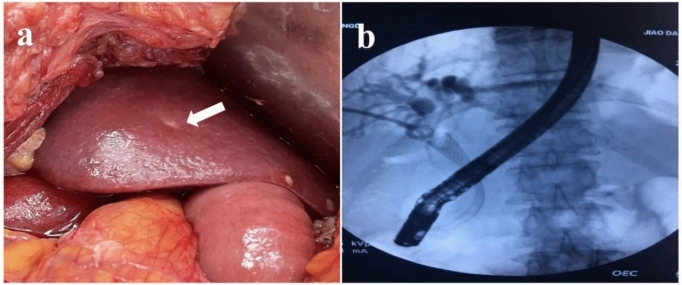

Case presentation: A 52-year-old male patient with pancreatic cancer and multiple liver metastases was reported. Imaging examination showed multiple low-density shadows in the liver. Laboratory tests showed elevated levels of pro-gastrin-releasing peptide and CEA. After gemcitabine combined with albumin-bound paclitaxel chemotherapy, the liver metastases disappeared and the primary pancreatic head tumor was significantly reduced. Pancreaticoduodenectomy was performed, and the patient recovered well without any other adjuvant therapy. The patient has been alive for 36 months without tumor recurrence.